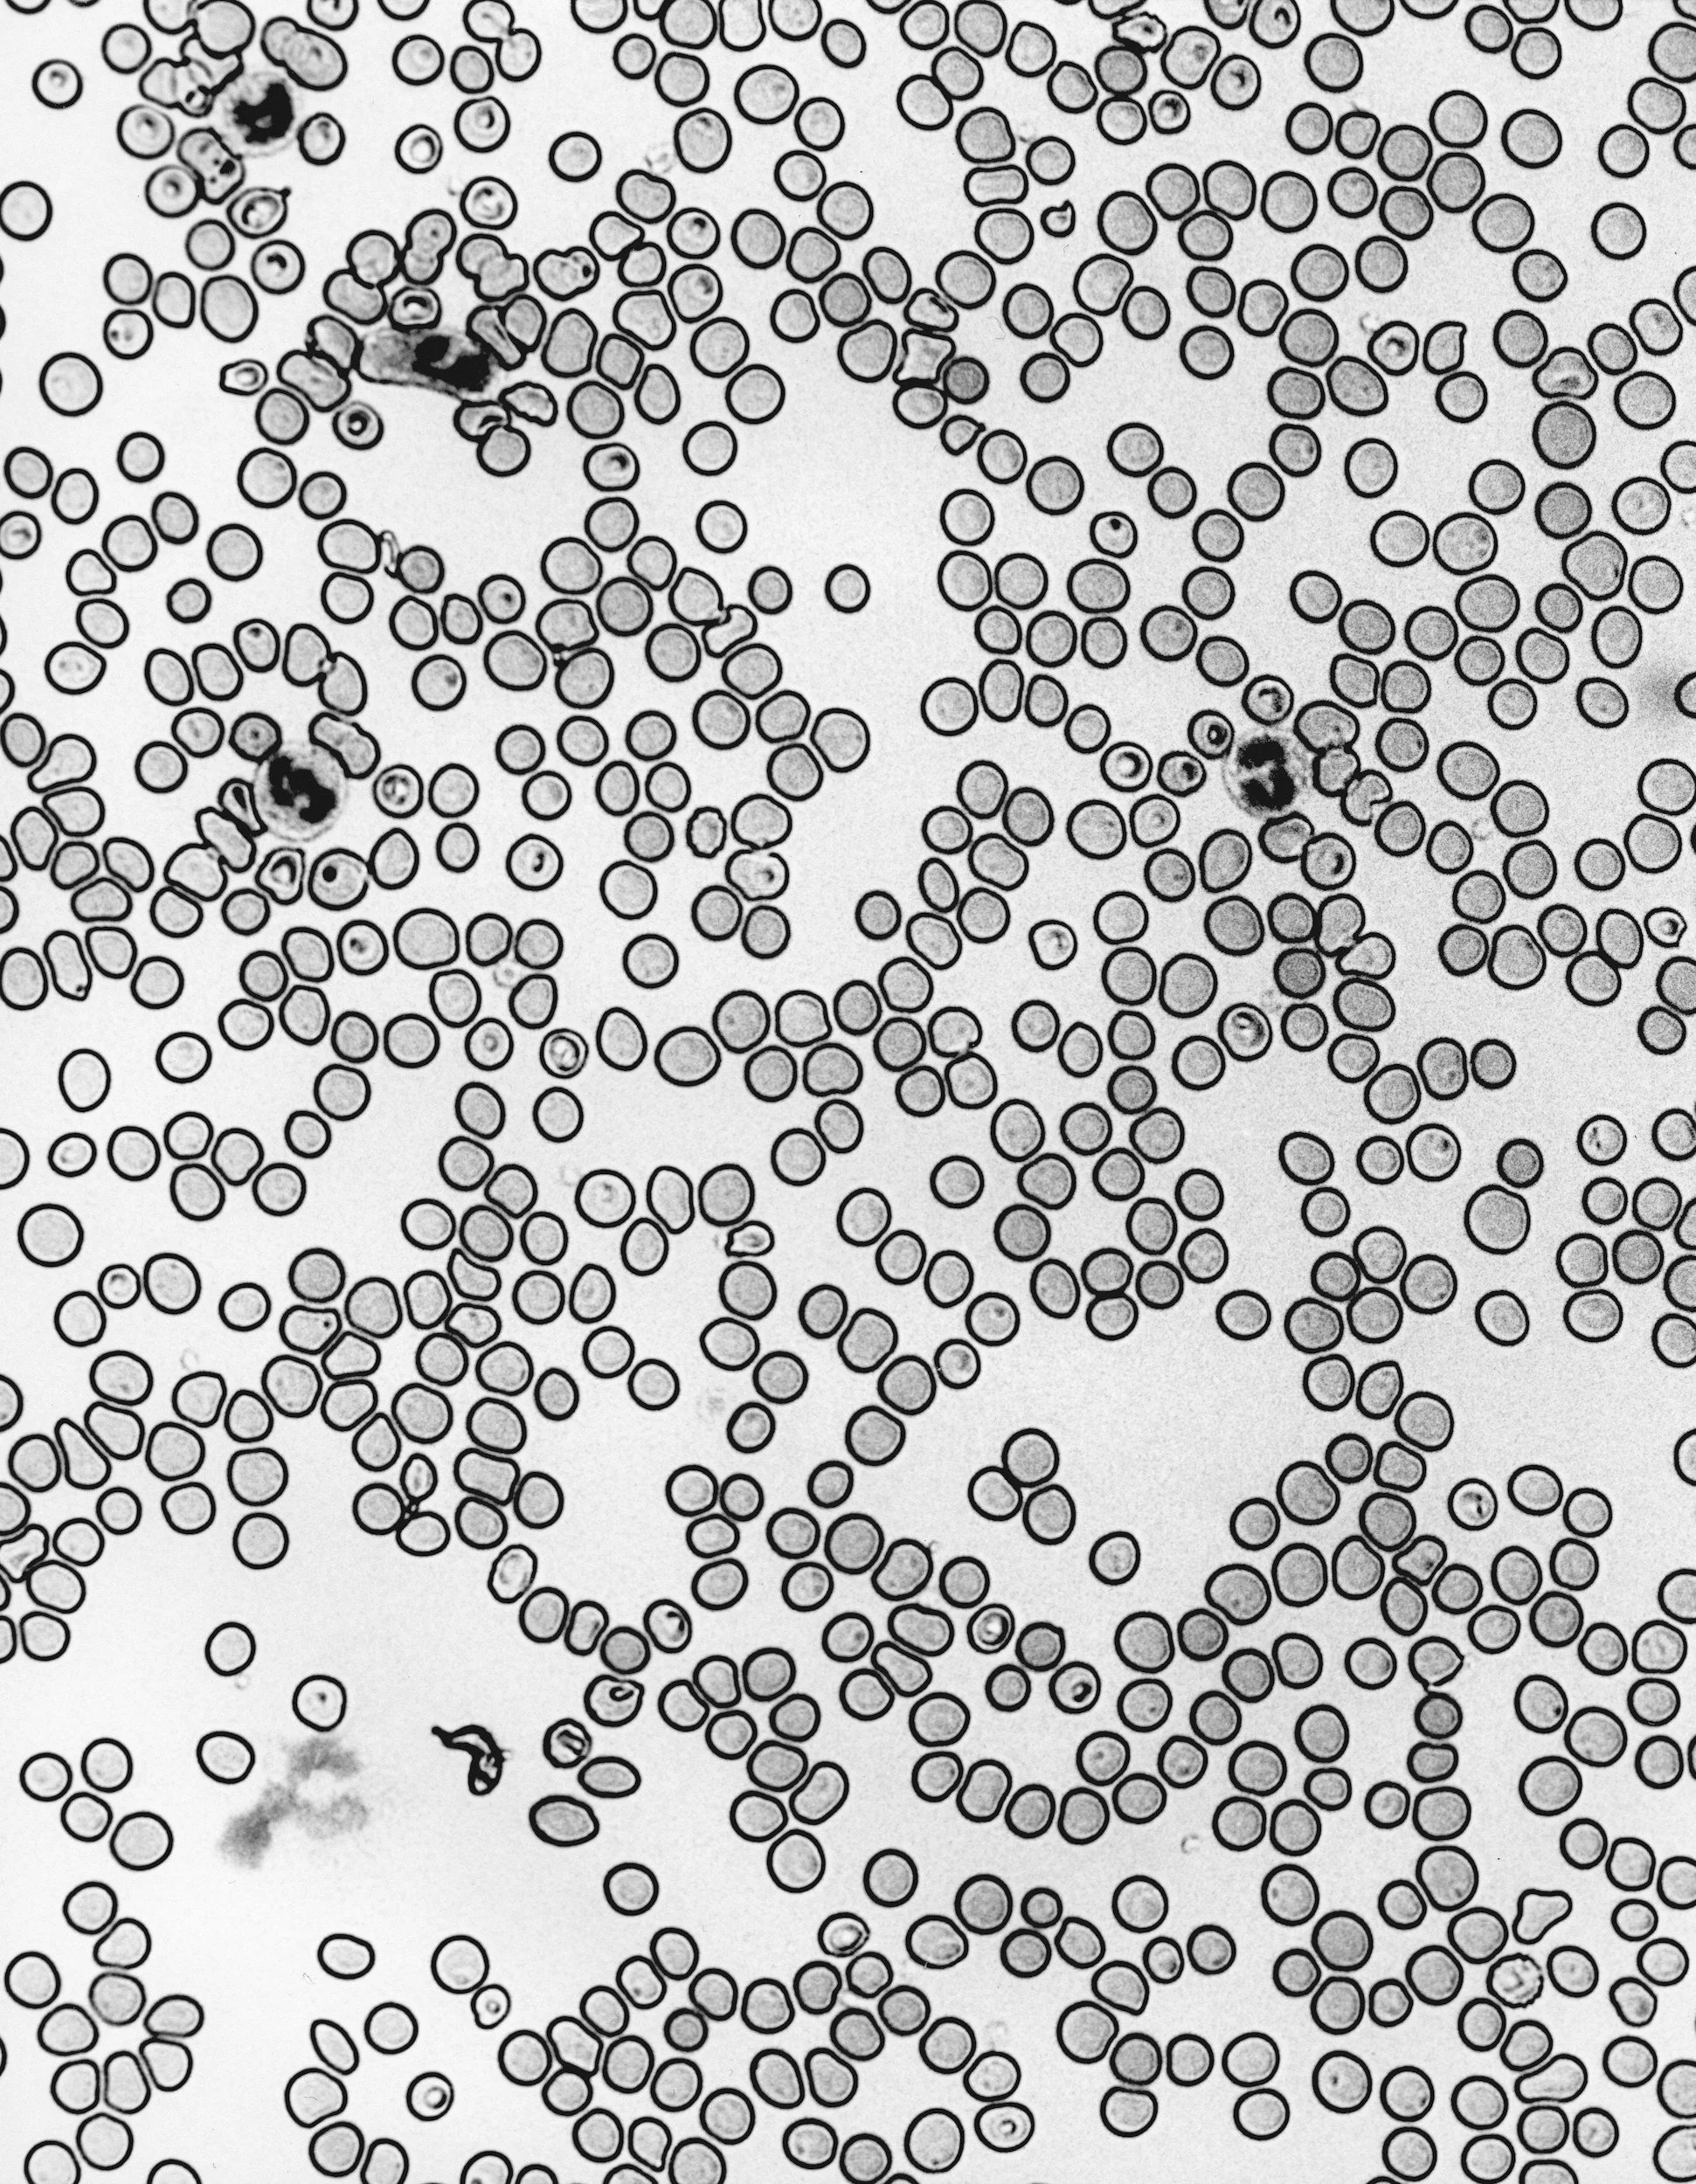

• Microscopic view of numerous red blood cells, some of which are in clusters and irregular shapes, with a few dark spots and debris scattered throughout.

Orthobiologics

Evidence-based spectrum of orthobiologic treatments including PRP, PPP, MFAT, and BMAC